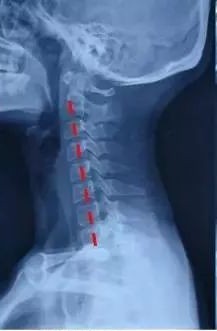

正常的颈椎是一个「C」型结构,颈椎有一个向前凸起,这是它的力学结构基础。这个「C」型的生理弧线保证了颈椎高度的灵活性和稳定性,这也是人体生理和功能的需要。也正是由于这个生理弧度的存在,使得组成颈椎的7块小骨头能够承担整个头颅的重量,并完成各种动作。颈椎曲度是由于颈4至颈5椎间盘前厚后薄形成的,这也是人体生理结构的需要,同时不会让颈椎间盘突出。

我有一个患者,因头晕头痛,容易劳累,前来就诊,查体后见:颈椎曲度变直,肌肉僵硬,压痛明显,转颈试验(-),臂丛神经牵拉试验(-),霍夫曼征(-)。

经一个月的推拿正骨结合功能锻炼治疗后,头晕头痛症状消失,复查X线片示:颈椎曲度基本恢复。